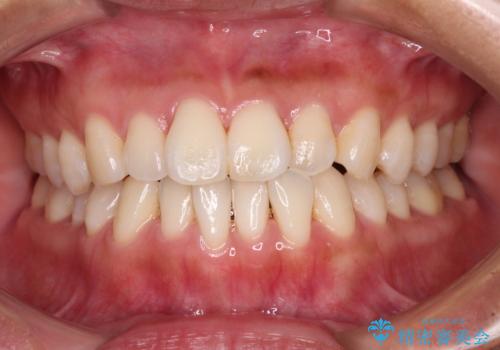

[ マウスピース矯正 ] 長期海外出張中に矯正治療を行いたい

![[ マウスピース矯正 ] 長期海外出張中に矯正治療を行いたいの症例 治療前](https://seimitsushinbi.jp/wp/wp-content/uploads/2023/04/IMG_9839-1-500x350.jpg?v=1682416148)